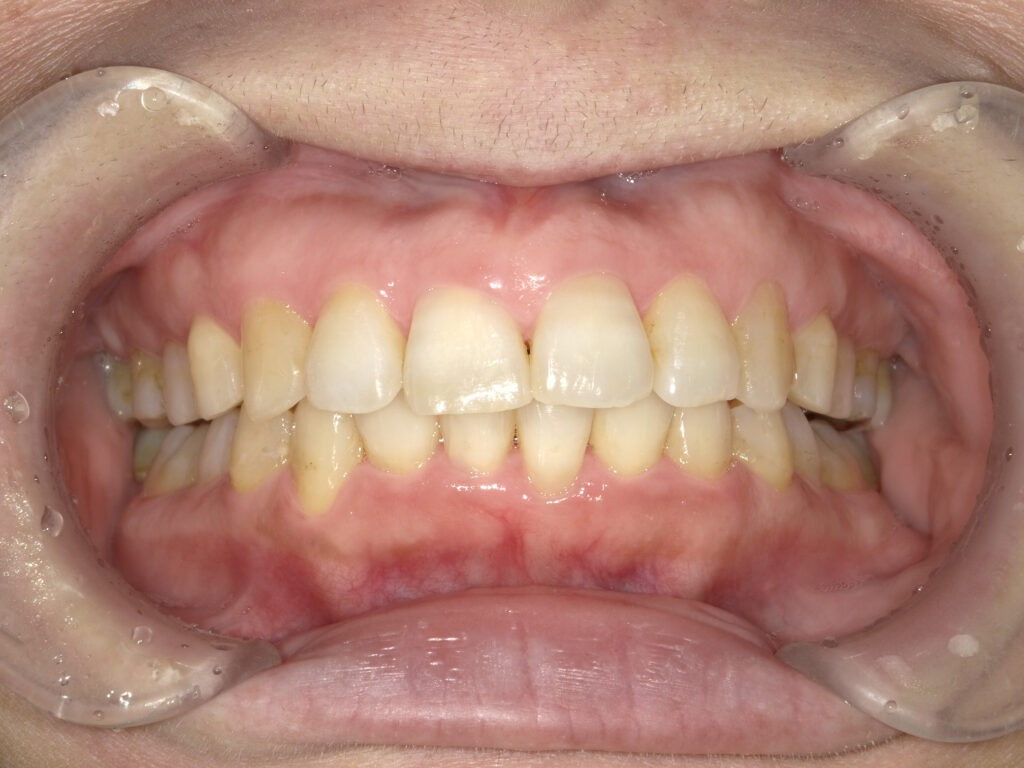

正面

治療前

治療後